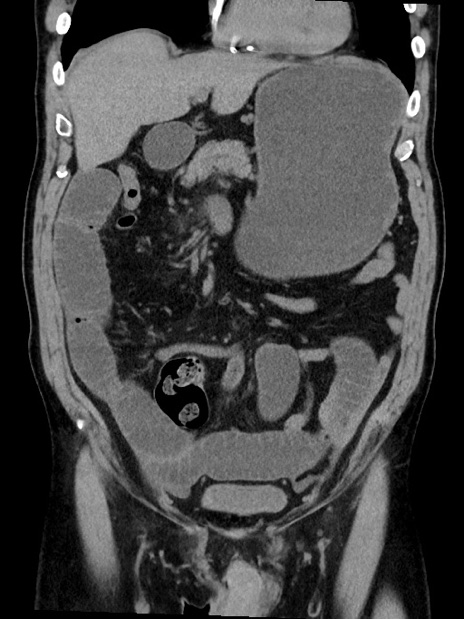

症例35(冠状断像)

【症例】70歳代 男性

【主訴】腹部膨満、嘔吐

【現病歴】昨日より腹部膨満感出現。本日増悪し、仙痛出現。嘔吐あり、受診。

【既往歴】糖尿病、胆摘後

【身体所見】BP 149/80mmHg、HR 74/min、BT 35.9℃、腹部:膨満、軟、圧痛なし。腸雑音減弱あり。上腹部正中切開瘢痕あり。

【データ】WBC 13500、CRP 1.72

横断像